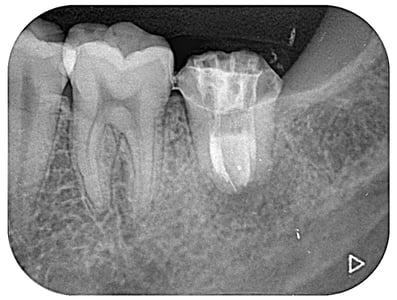

術後5年経過症例。樋状根は抜歯と判断されることが多いようですが、当院ではあきらめずに治療して良い成績を残しています。(7番の近心には、金属修復物下に虫歯があります。他院で定期健診を受けていたようですが、メンテナンスの仕方に問題はなかったでしょうか?)

約1ケ月後ですが、根の先の炎症の証である透過像は、消失し、噛むと痛いなどという臨床症状も消えました。